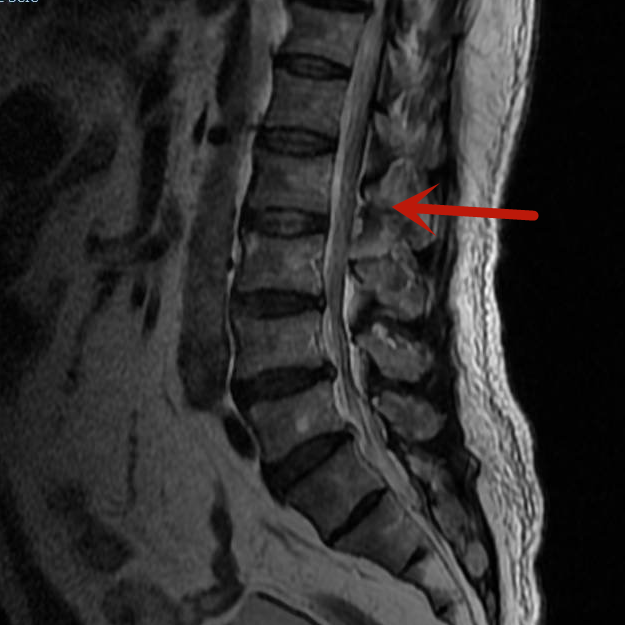

术后影像

术后第1天,梁先生便可下床活动,没有出现手术并发症。3天后,梁先生就康复出院了,他激动地说:“感谢市人民医院脊柱骨科团队,一个小小的切口就解决了我的大麻烦,你们的医术真精湛!”